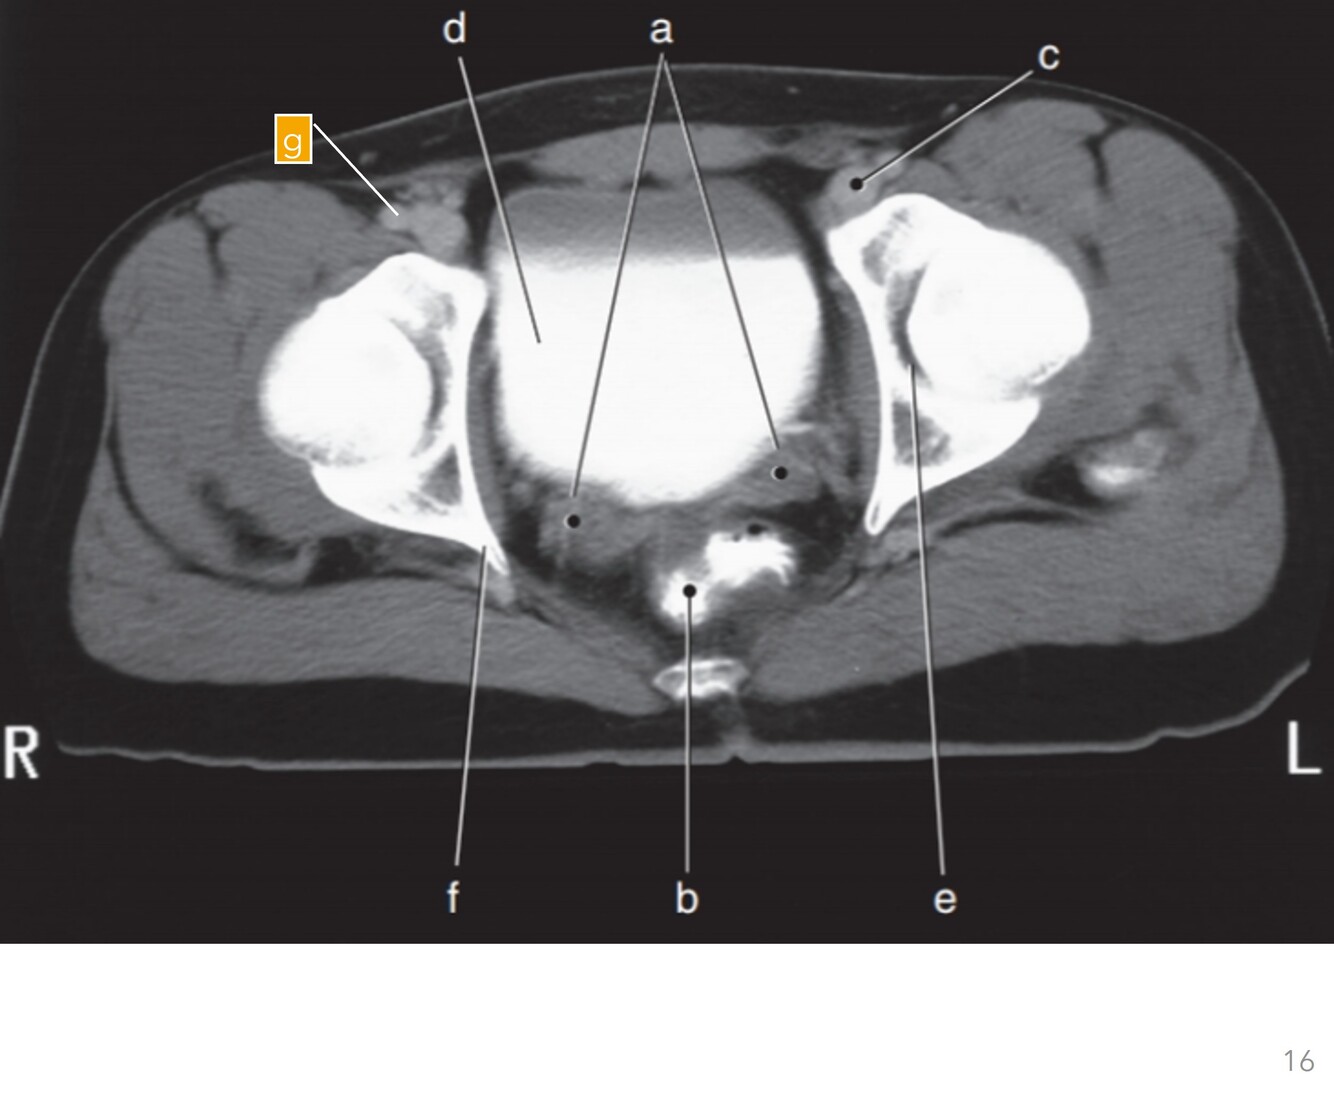

Label a-g

A

a-Seminal vesicles

b-Rectum

c-Lt femoral vein

d-Bladder

e-Lt acetabulum

f-Rt ischial spine

g-Rt femoral artery